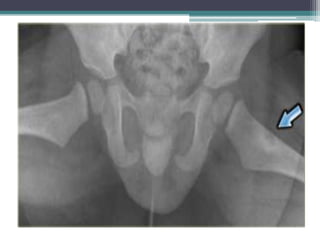

M.O. EN Rx. PELVIS

APENAS VISIBLE EN

HUESO ILÍACO

IZQUIERDO.

EN TC. SE OBSERVAN

LAS LESIONES CON

MEJOR DEFINICIÓN.

M.O. EN Rx.PELVIS APENAS VISIBLE EN HUESO ILÍACO IZQUIERDO. EN TC. SE OBSERVAN LAS LESIONES CON MEJOR DEFINICIÓN.